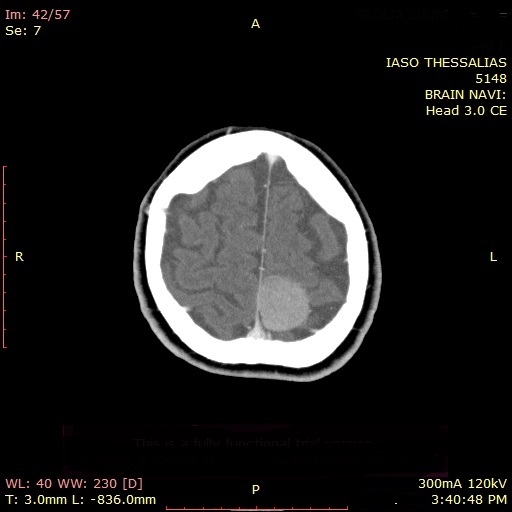

Στη συνέχεια, ο Νευροχειρουργός, Ιορδάνης Γεωργιάδης, Επιμελητής της Α’ Νευροχειρουργικής Κλινικής του ΙΑΣΩ Θεσσαλίας, εξέτασε την ασθενή και σύστησε, σε συνεργασία με την Αναισθησιολόγο Ελευθερία Τουτουνοπούλου, χειρουργική αντιμετώπιση με σκοπό την ολική εξαίρεση του όγκου, με τη μέγιστη δυνατή ασφάλεια. Η ασθενής οδηγήθηκε στο χειρουργείο και τέσσερις ημέρες μετά έλαβε εξιτήριο για την οικία της με τις απαραίτητες οδηγίες. Στο πλαίσιο επανελέγχου με αξονική τομογραφία (με σκιαγραφικό) που πραγματοποιήθηκε δύο μήνες μετά, διαπιστώθηκε πλήρης εξαίρεση του καλοήθους όγκου και άριστη νευρολογική εικόνα της ασθενούς.

Απεικονιστικά, η πρώτη εξέταση που συνήθως ανευρίσκεται ένα μηνιγγίωμα είναι η αξονική τομογραφία εγκεφάλου, ενώ η εξέταση εκλογής είναι η μαγνητική τομογραφία με χορήγηση παραμαγνητικής ουσίας. Επιπλέον, η μαγνητική φασματοσκοπία πρωτονίου (MRS) δίνει στον Νευροχειρουργό πληροφορίες για τα μεταβολικά χαρακτηριστικά του μηνιγγιώματος.